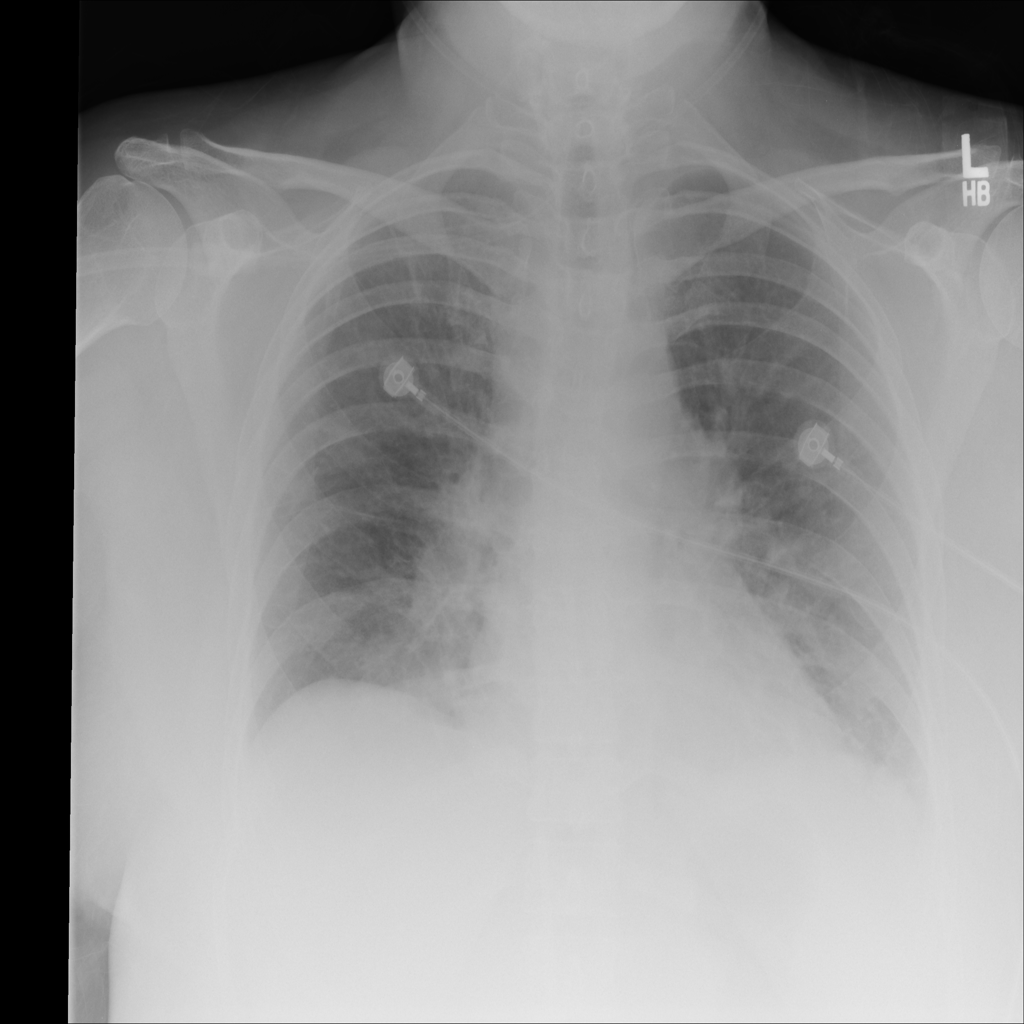

PAT-24D9 · IMG-006Edema

PAT-24D9 · IMG-006

AP